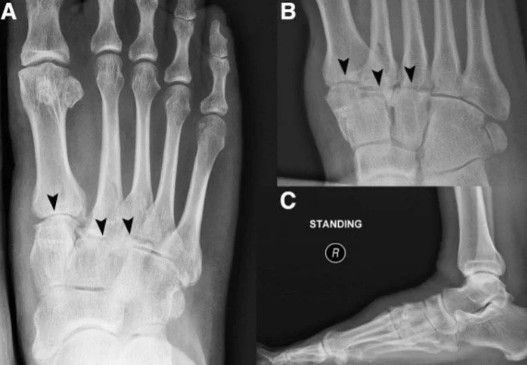

- Radiografias (Raio-X): São os primeiros exames solicitados. Eles podem revelar o estreitamento do espaço articular (indicando perda de cartilagem), a presença de osteófitos (bicos de papagaio) e alterações na estrutura óssea.

- Ressonância Magnética (RM) ou Tomografia Computadorizada (TC): Podem ser solicitadas para avaliar a cartilagem, identificar edemas ósseos e visualizar outras estruturas em maior detalhe, ajudando a planejar o tratamento.